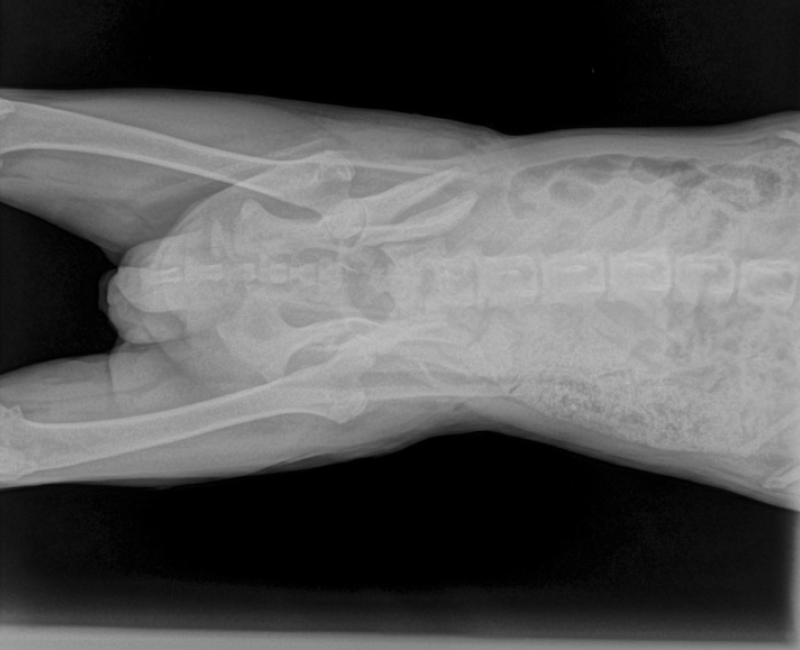

Se le llevó urgentemente al veterinario, donde realizaron placas y le amputaron la cola prácticamente en su totalidad, por la infección que tenía incluso con gusanos. Y obviamente radiografías, ambas caderas partidas, pero no se observaba el callo tan grande que había generado en este tiempo, así que después de abrir decidieron, seguir dejándolo soldar a su ritmo, más que volver a romper todo, placas, tornillos,….